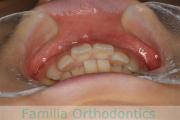

- ≫治療前

-

上顎

下顎

前歯の関係など

右側

正面

左側

- ≫治療後

下の前歯が後ろにあるのが気になるとのことで来院されました。非抜歯で行うことも可能でしたが、上下左右から小臼歯抜歯をして治療を行うことをご希望になりました。

マルチブラケット法にて治療を行い、約3年、40回の通院が要でした。

かみ合わせが深い(上の前歯で下の前歯が覆われてしまう)ので、保定をしっかりしないと、また深くなってきてしまいやすいです。